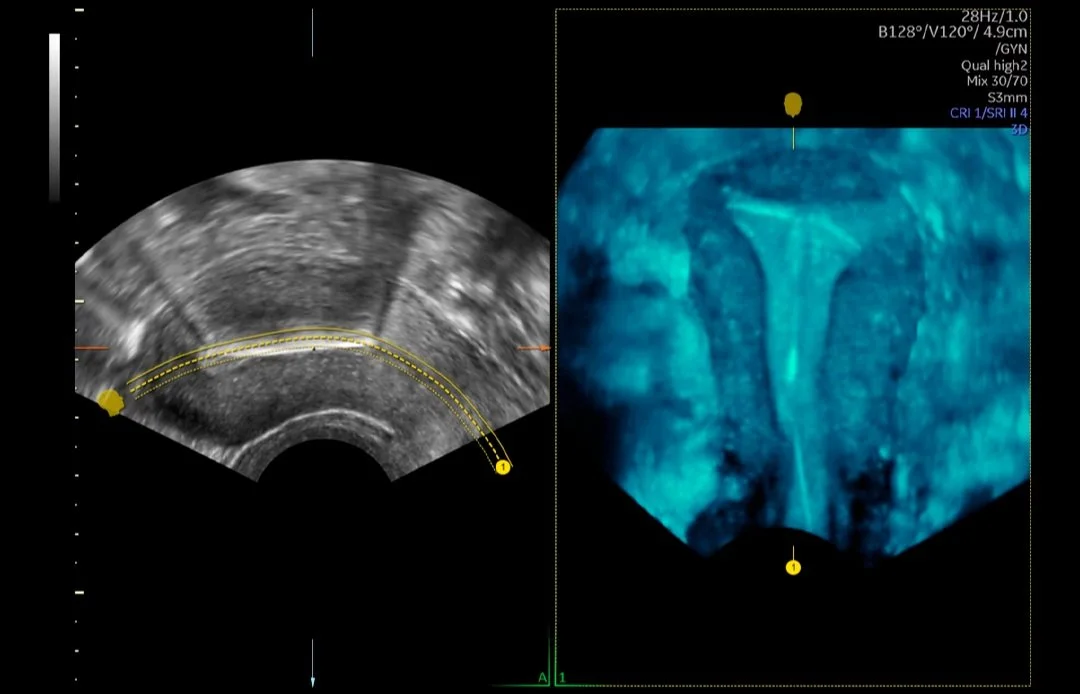

Diagnóstico pormenorizado

El proceso de parto está lleno de emoción, expectativas y, a veces, incertidumbre. Con imágenes extraordinarias y seguimiento innovador de la evolución del parto, Voluson SWIFT puede ayudarlo a controlar la progresión del parto, así como el bienestar tanto del bebé como de la madre, lo que lo ayuda a tomar decisiones clínicas más informadas.